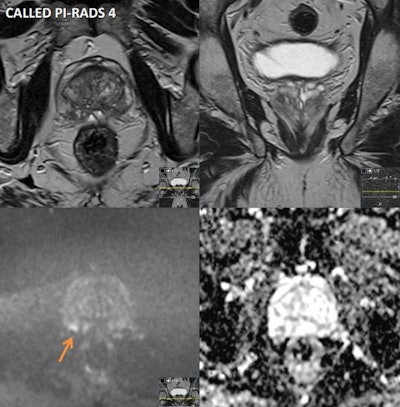

A 70-year-old asymptomatic man had a prostate-specific antigen (PSA) level of 2.67 in 2013, 3.13 in 2018, and 6.38 on August 2021. He had a Gleason Score of 3+4 pT3a, R1 left apex margin. Multiparametric MRI was performed on a 1.5 tesla scanner. Prostate volume was 33 cc and PSA density was 0.19. Peripheral zone (PZ): patchy intermediate signal bilaterally with a 6 mm focus of restricted diffusion and early enhancement in the right posterior base (see annotated images), PI-RADS 4 / LIKERT 4. Transition zone (TZ): no suspicious focal lesions. Extraprostatic extension: not evident. Seminal vesicles: normal. Lymph nodes: none enlarged. Bones: no suspicious focal lesions. Incidental finding: 12 mm polypoid lesion in the mid to lower rectum (annotated image) will require colorectal review and endoscopic correlation. Conclusion: small PI-RADS 4 lesion in the right posterior PZ will require a targeted biopsy. If malignancy is proven histologically, suggested radiological staging would be T2N0Mx. Figure courtesy of Prof. Anwar Padhani, from "AI - Human Workflows NoteBookLM" podcast.